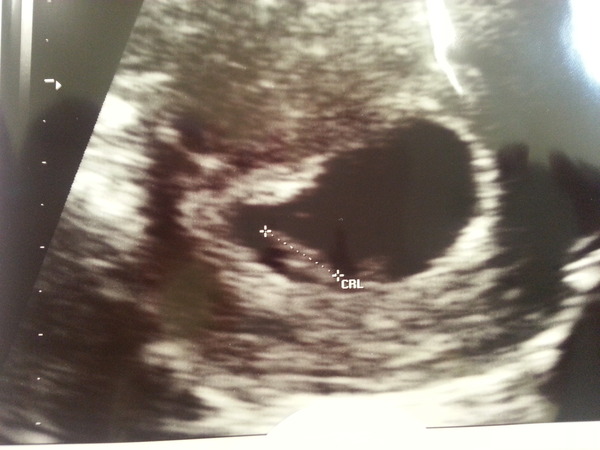

Hi all! Sorry I haven't been around much, have been trying to keep up with the thread though! I am now 9+3. Have been feeling a lot better this week, still tired though. I didn't realise that you could upload pictures, I have added our scan pic which was taken last week at 8+2.

Bouncesky, lovely picture! Grin How exciting! Congrats on your upcoming wedding too!

bounce I was 7 +5. The blob measured 1 cm with heartbeat which put me at 7 +1 but I am sticking with my original dates until dating scan in September. And according to my app the blob is now technically a foetus!